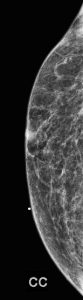

A bilateral diagnostic mammogram was performed. Images of the right breast shown here do not demonstrate any mammographic abnormality under the BB skin marker:

Explanation: This is a circumscribed, oval, hyperechoic mass, which is consistent with a lipoma. They have the same imaging appearance in males and females. They may appear as circumscribed fat-containing masses on the mammogram, particularly if the patient has a lot of fibroglandular tissue. Since this male’s breast is composed predominantly of fat density, the lipoma cannot be easily discerned on the mammogram. On ultrasound, a lipoma (arrows) is either isoechoic or slightly hyperechoic to the surrounding subcutaneous fat (*). Lipomas are benign and when correctly identified on imaging, they do not require further follow-up.